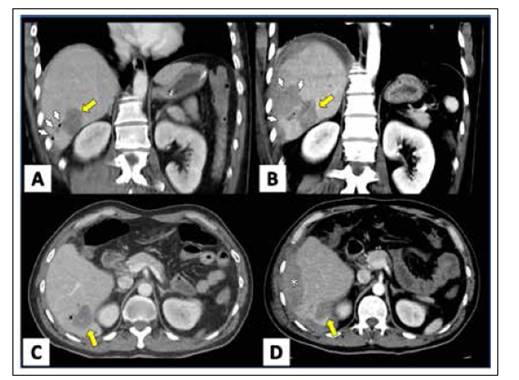

En la primera tomografía contrastada 24 horas post CPRE (ver Figura 1) se aprecia focos hipodensos en segmento hepático III de 16 mm x 23 mm, segmento IV de 39 mm x 45 mm con 2 pequeños focos aéreos en su interior menores de 4 mm con presencia de aire en el interior de la vía biliar y líquido libre laminar en espacio perihepático.

Figura 1 MPR curvo en coronal de TC abdomen con contraste, A/C. 24 horas y B/D. 72 horas. Se identifica hematoma intraparenquimal (fecha amarilla) adyacente a laceración hepática (flechas blancas). Nótese la formación de hematoma subcapsular (asterisco en D) así como mayor amplitud de la laceración. Hallazgos en relación a Trauma grado III.

Durante la evolución el paciente resuelve el dolor abdominal casi en su totalidad, permanece con funciones vitales estables, no desarrolla episodios de hematemesis ni melenas ni otra evidencia de sangrado activo. Dos días posterior a la CPRE paciente presenta hematocrito control de 29,2%, 4 puntos inferiores que el previo, siendo evaluado mediante ecografía abdominal encontrándose una colección intraparenquimal hepática en segmentos VII y VIII asociados a hematoma subcapsular. Un día después la segunda tomografía (ver Figura 1) permite observar focos heterogéneos de gran extensión siendo denominados como colección intraparenquimal y subcapsular.